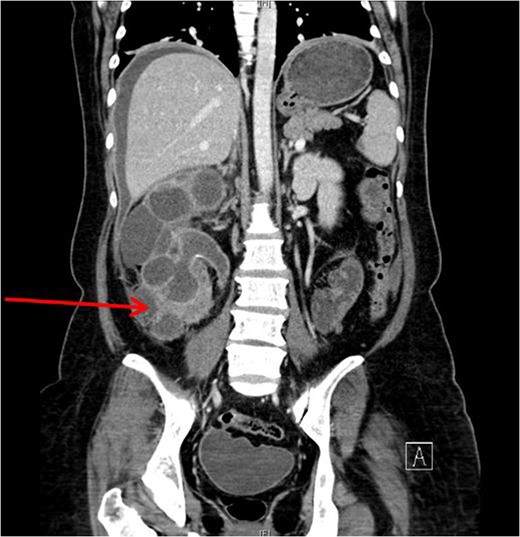

She underwent insertion of a right percutaneous nephrostomy drain, percutaneous drainage of the anterior abdominal collection, as well as a percutaneous biopsy of the right renal soft tissue lesion. Urine cultures from the percutaneous nephrostomy grew Proteus mirabilis. Fluid cytology from the abdominal collection showed acute inflammatory cells. Biopsy of the renal lesion showed xanthogranulomatous inflammation.

After a period of antibiotic treatment, she underwent open right nephroureterectomy with exploration, drainage and washout of the preperitoneal collection. During surgery, 1 l of pus was drained from the preperitoneal space, and cultures grew P. mirabilis. The ureter was ligated below the level of the calculus and removed together with the kidney. Final histopathology results showed XGPN with no evidence of malignancy in the kidney or peritoneal lining.

Our patient had an atypical presentation with abdominal distension and presumed ascites, which was eventually revealed to be an anterior preperitoneal collection secondary to infection. Although the initial suspicion was that of a malignant process complicated by ascites, subsequent cytology and histopathological results showed that it was likely benign. In view of the non-functioning renal unit and significant abdominal collection, she underwent definitive surgery.

The most common urinary pathogen identified was Escherichiacoli [3], and common areas of involvement were the retroperitoneum and psoas muscle. In our patient, the retroperitoneal space was surprisingly not greatly involved, but rather it was the anterior preperitoneal space that had significant adhesions and inflammation. The pathogen identified from both nephrostomy and preperitoneal collection was P. mirabilis, showing that both pathologies were linked.